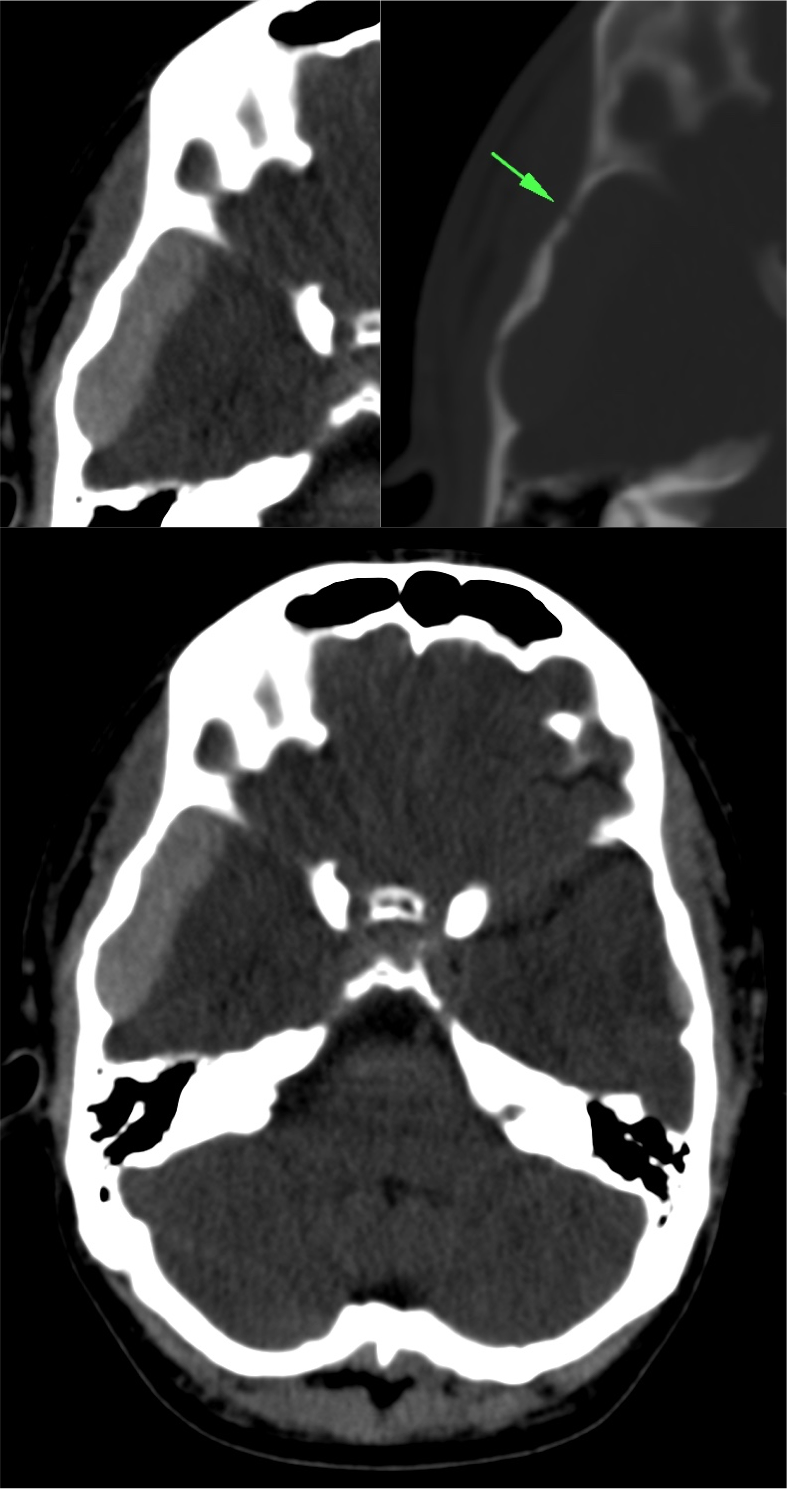

Con ventana de hueso.

Las reconstrucciones 3D-VR aumentan la capacidad diagnóstica de las fracturas desplazadas y no desplazadas.

La presencia de fractura no se correlaciona con la severidad del daño cerebral, sin embargo, la incidencia de hemorragia intracraneal es mayor en pacientes con fractura que en los que no la presentan. Al mismo tiempo, el 25% aprox. de pacientes con daños cerebrales fatales no muestran fractura de cráneo.

- Fracturas lineales = las más frec. -> baja incidencia de daño cerebral.

- Fracturas con hundimiento -> asocia contusiones y roturas durales.

- Fracturas de la base -> pueden ser transversas o diagonales, éstas con mayor índice de mortalidad. Pueden causar ceguera, afectación de pares craneales, pédida de audición, fuja de LCR. En las fracturas que afectan al canal carotídeo en su porción petrosa, merece la pena realizar un angioTC.